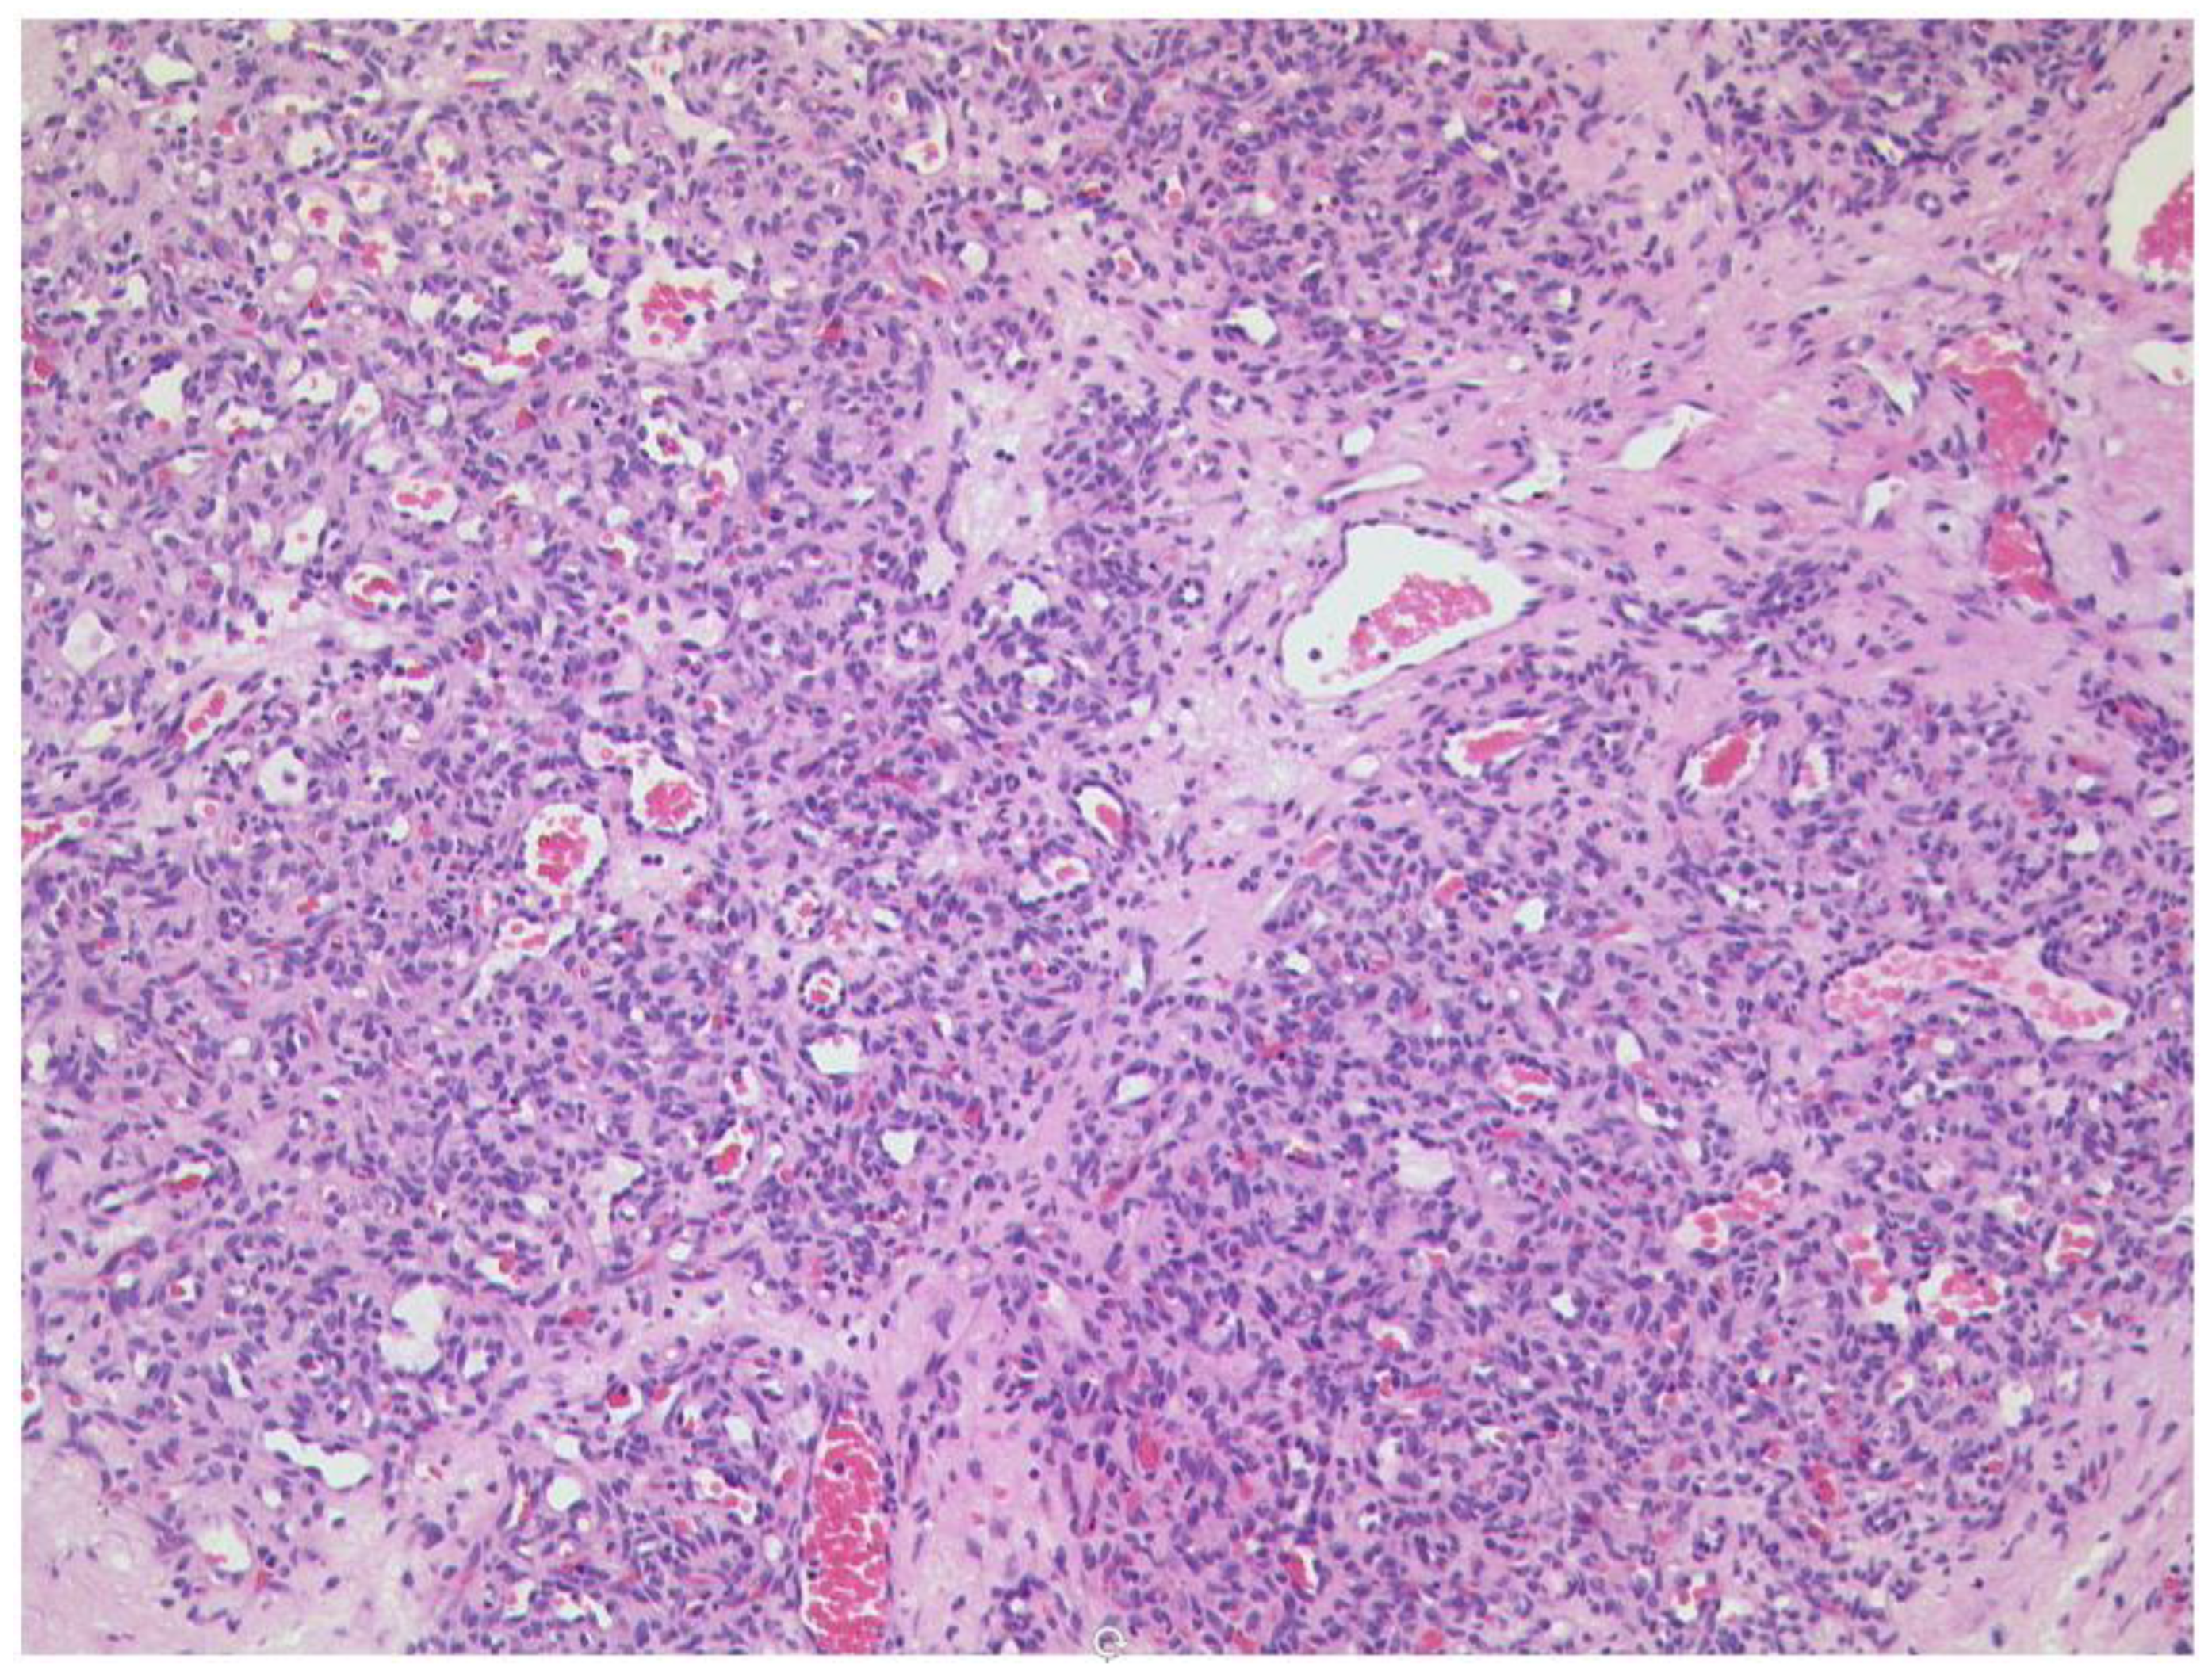

3.6.2. Rhabdomyosarcoma

- Inarejos Clemente, E.J.; Navallas, M.; Barber Martínez de la Torre, I.; Suñol, M.; Munuera Del Cerro, J.; Torner, F.; Garraus, M.; Navarro, O.M. MRI of Rhabdomyosarcoma and Other Soft-Tissue Sarcomas in Children. Radiographics 2020, 40, 791–814. [Google Scholar] [CrossRef]